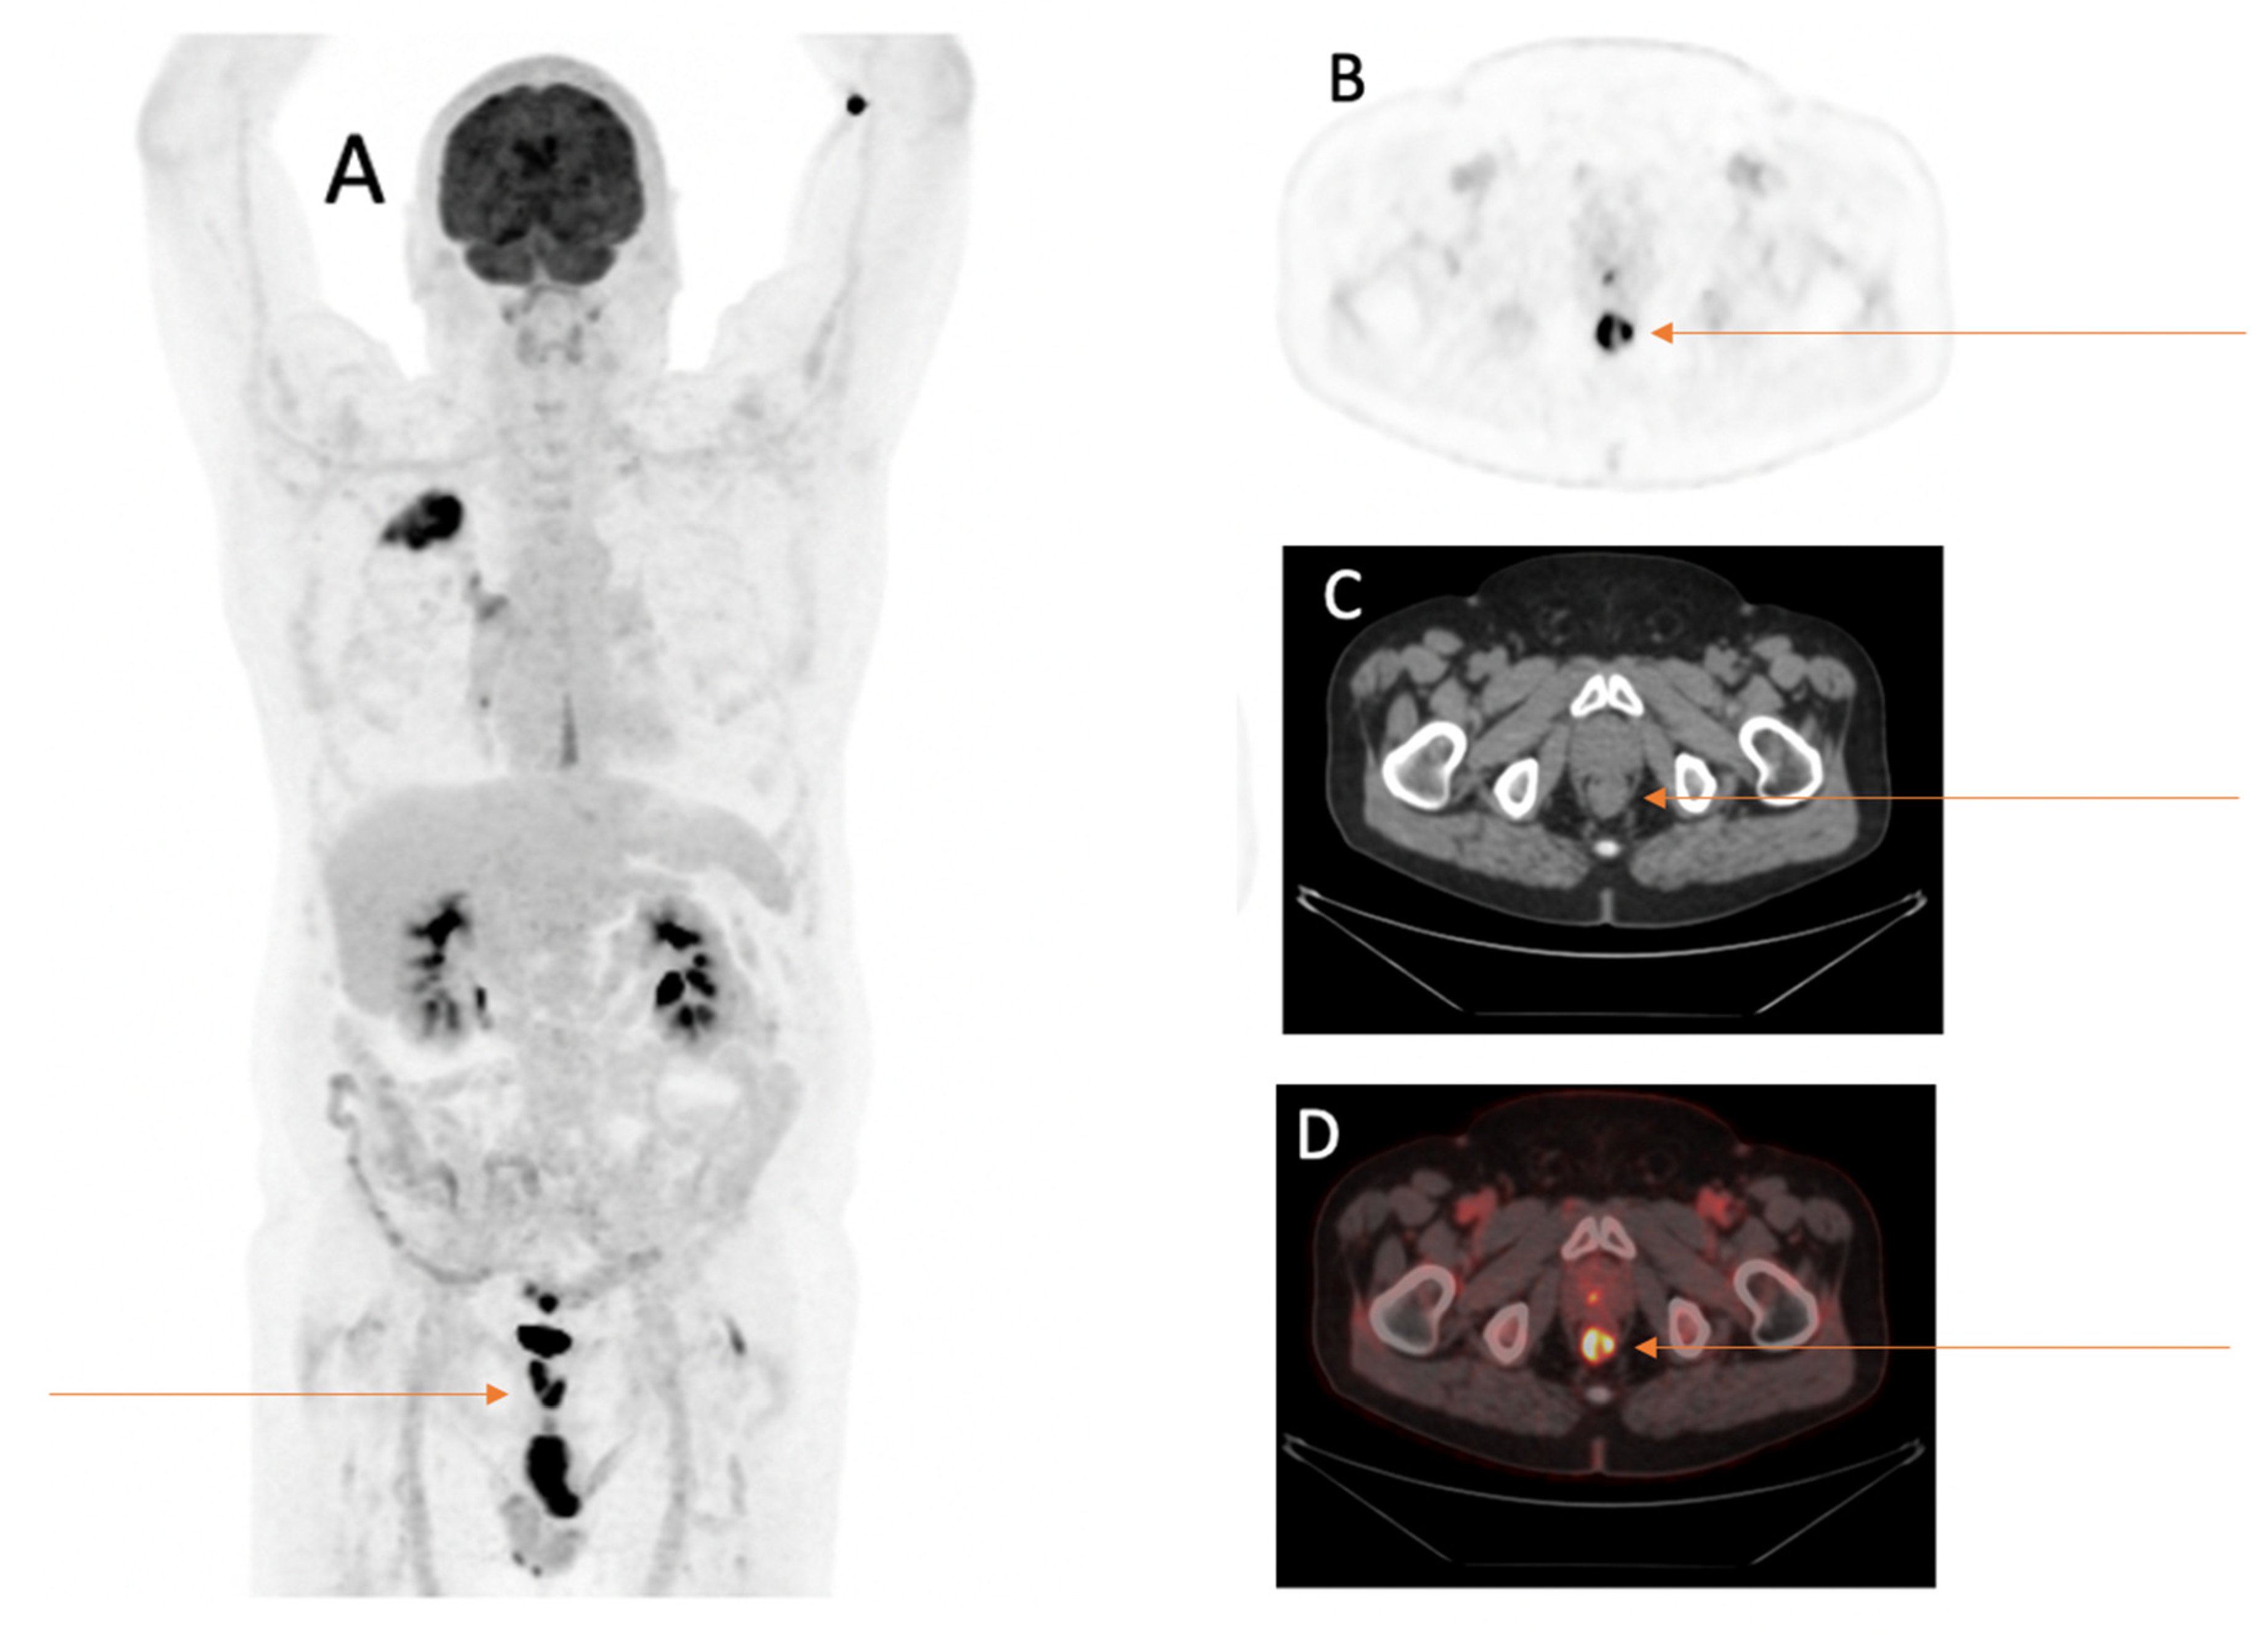

Figure 2.

Sixty-nine-year-old male patient with first diagnosis of NSCLC (TTF1 positive adenocarcinoma of the right lower lobe pT2a, pN0, M0) underwent FDG-PET/CT for staging. FDG-PET/CT scan displayed an incidental FDG-avid wall thickening of the rectum. (A) MIP image after the intravenous injection of 245 MBq 18F-FDG. (B) PET image of the rectum. (C) CT image of the rectum. (D) Fused PET/CT image of the rectum. After further investigations following the FDG-PET/CT, the wall thickening was histopathologically confirmed as microsatellite stable adenocarcinoma of the rectum T3 cN2 cM0, 5 cm oral to the anus.